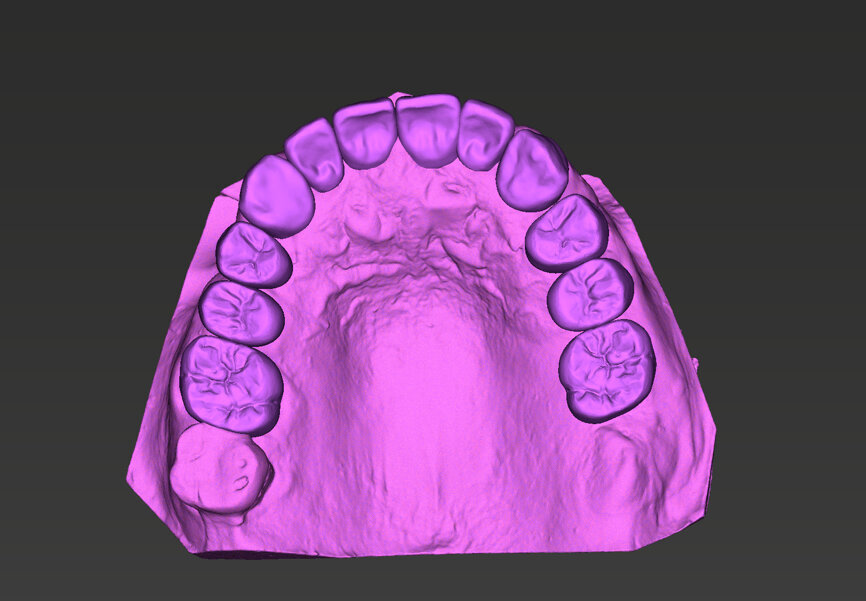

A 51-year-old male patient who was a smoker (< 10 cigarettes per day) and in good general health presented to the clinic with missing molars in the second and fourth quadrants, Grade III mobility of teeth #24 and 17, decayed roots and gingival inflammation, and without abscess or sinusitis of tooth #16. The anterior zone showed  different extents of recession, bone resorption and deep periodontal pockets around teeth #12 and 22, which led to the patient complaining about an aesthetically unsatisfying restoration (Figs. 1 & 2).

An intra-oral scan was taken to record the patient’s current oral situation, and the resulting STL file and the DSD fil (2D smile design image) were used to create the future prosthetic design with software for the laboratory (Figs. 3–6). The 3D radiographic DICOM data and the prosthetic design project STL file were superimposed in coDiagnostiX (Figs. 7–9) The fixation pin guide, bone reduction guide, surgical guide and bite registration guide were designed with coDiagnostiX (Figs. 10–13) and produced using 3D printing technology.